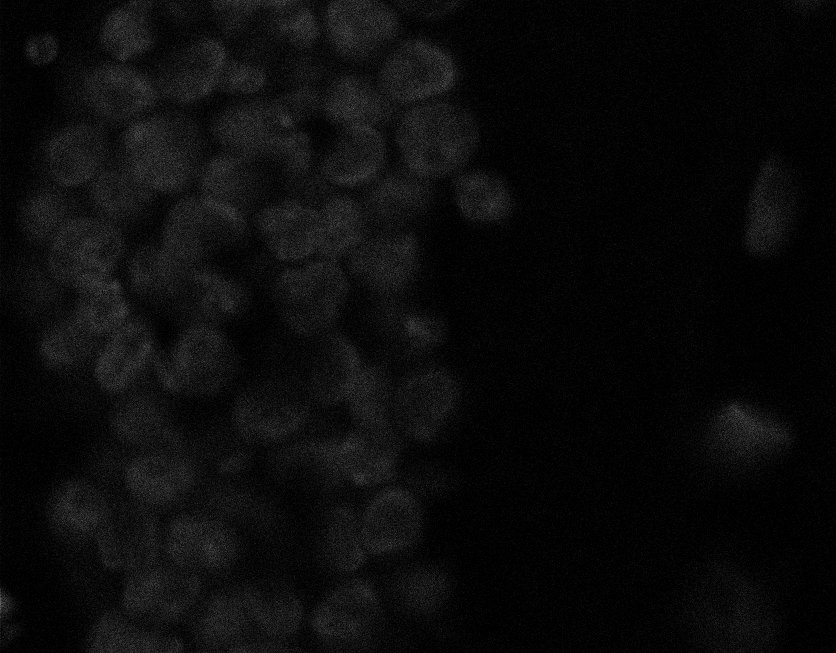

Actin

Nuclei